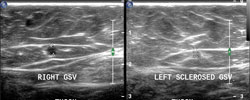

"До" и "после" лечения.